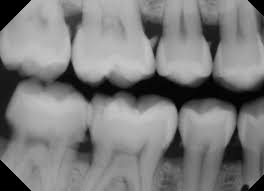

The dentistry project, as we so called, concerns a type of dental X-ray sensor called Phosphor Storage Plates (PSPs) which are very commonly used because of its easy placement in the oral cavity and the resulting minimum discomfort. The sensors, however, can accumulate damages over time, which would show up in the final image as artifacts with various appearances. Such artifacts could get in the way of diagnosis; thus, the plates need to be discarded before it’s too damaged. But how damaged is too damaged? For the moment, nobody has answers to that. Our goal is to use machine learning to learn the relationship between artifacts and whether they would affect diagnosis. Eventually, we can use that model to make predictions for a given plate and offer dentists advice as in when to discard it. The entire project is huge and the part we played in this summer mainly contributes as preparatory work. We segmented the artifacts from the image and clustered them into five groups based on 9 hand-engineered features. This characterization of the single artifacts can serve as the input for the model. We also created a library of superimposed images of artifact masks and real teeth backgrounds to mimic images taken with damaged sensors in real clinical settings. We did this so that dentists can take a look at these images and give a diagnosis. Comparing that with the true diagnosis, we can obtain the labels for whether a given artifact will affect diagnosis or not. And this will be the output of the model. The testing of these images is currently underway, and the results will be available in early September for further analysis.